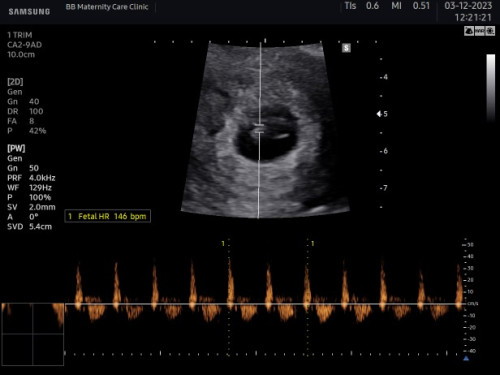

เมื่อต้นปี65น้องลืมของเล่นไว้ ตอนนี้น้องกลับมาแล้วค่ะ ดีใจมากเลย ตอนได้ยินเสียงหัวใจ 💓💓